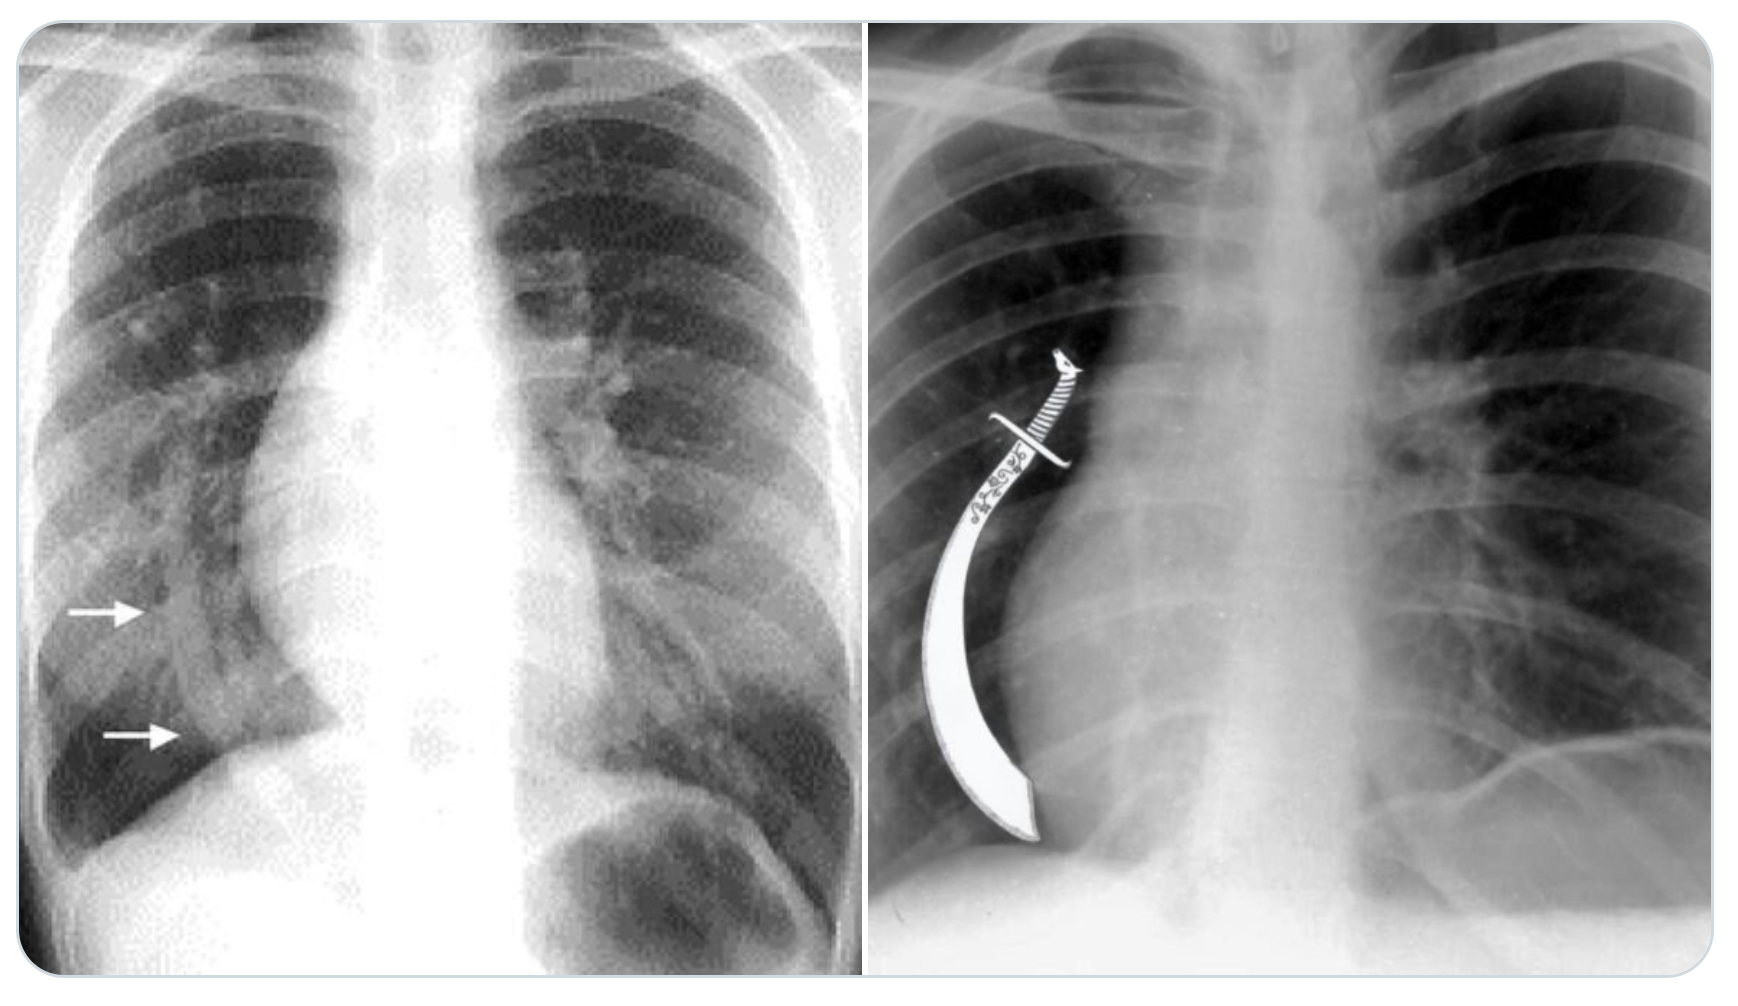

- カルディオメムス(CardioMEMS)というワイヤレス肺動脈圧モニターがある